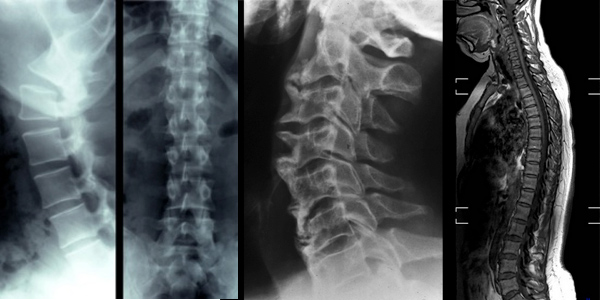

LOMBER DİSK HERNİSİ ( BEL FITIĞI )

SERVİKAL DİSK HERNİSİ ( BOYUN FITIĞI )

SPONDİLOLİSTEZİS ( BEL KAYMASI )

OMURİLİK KANALI DARLIĞI ( SPİNAL STENOZ )

SKOLYOZ, KİFOZ ( OMURGA EĞRİLİKLERİ )